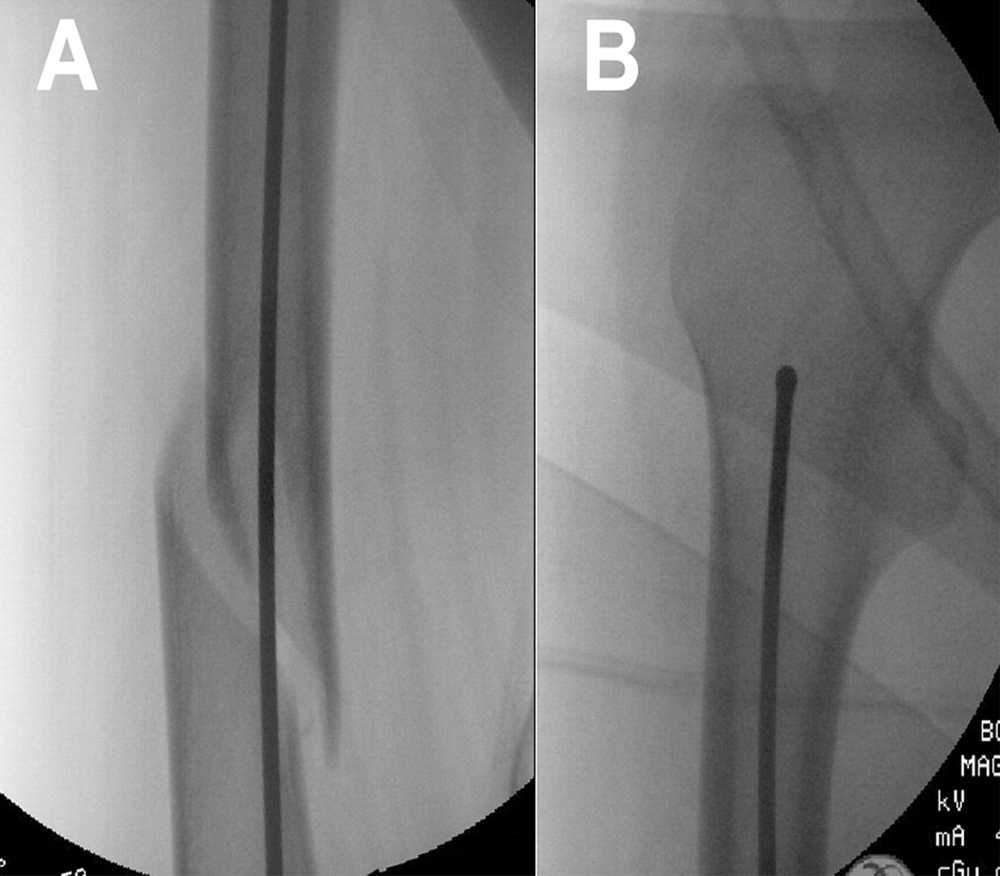

Kategorin omfattar osteosyntesmaterial för ortopedi, såsom skruvar, plattor, märgspikar med mera – produkter som används för stabilisering och läkning av frakturer samt rekonstruktion av skelettets strukturer.